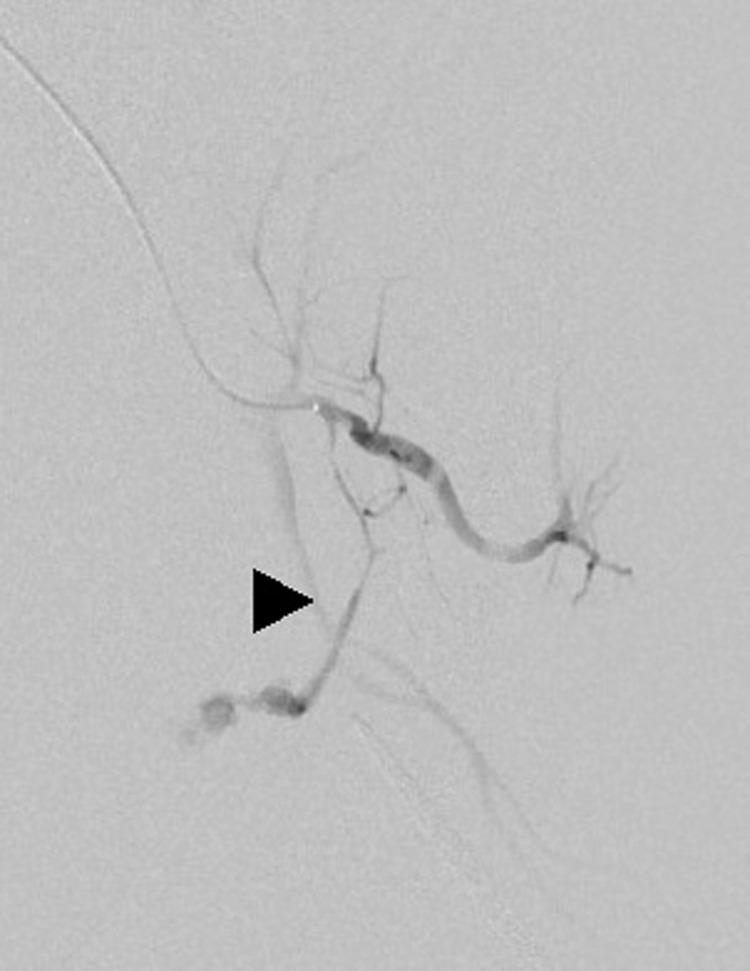

Post-surgical pseudoaneurysm in the pelvis is rare. However, when it does occur, it may cause life-threatening hemorrhage. Hemostatic treatment for pelvic pseudoaneurysms may be complicated because the blood vessels in the pelvis may present with various anastomoses. Herein, we describe a case of a pseudoaneurysm that necessitated embolization of two arteries. A 47-year-old woman had undergone a total hysterectomy, a bilateral adnexectomy, and a pelvic lymphadenectomy for endometrial cancer; 13 days after surgery, she complained of sudden abdominal pain. Contrast-enhanced computed tomography revealed a retroperitoneal hematoma and a pseudoaneurysm with contrast leakage. The pseudoaneurysm had two feeding arteries (from the external and internal iliac systems). The first feeding artery was the obturator artery, which arose from the anterior trunk of the internal iliac artery. The second feeding artery was the aberrant obturator artery, which arose from the medial femoral circumflex artery. Both feeders were embolized and hemostasis was achieved. Pseudoaneurysms in the pelvis may have double origins from the external and internal iliac systems, and the aberrant obturator artery may arise from the medial femoral circumflex artery. Therefore, radiologists should be aware of these variations to effectively address post-surgical pseudoaneurysms of the corona mortis artery.

盆腔术后假性动脉瘤较为罕见。然而,一旦发生,可能导致危及生命的出血。盆腔假性动脉瘤的止血治疗可能较为复杂,因为盆腔血管存在多种吻合情况。在此,我们描述一例需要栓塞两条动脉的假性动脉瘤病例。一名47岁女性因子宫内膜癌接受了全子宫切除术、双侧附件切除术和盆腔淋巴结清扫术;术后13天,她主诉突发腹痛。增强计算机断层扫描显示腹膜后血肿和一个有造影剂外漏的假性动脉瘤。该假性动脉瘤有两条供血动脉(分别来自髂外和髂内系统)。第一条供血动脉是闭孔动脉,起自髂内动脉前干。第二条供血动脉是异常闭孔动脉,起自股内侧旋动脉。两条供血动脉均被栓塞,实现了止血。盆腔假性动脉瘤可能有来自髂外和髂内系统的双重起源,且异常闭孔动脉可能起自股内侧旋动脉。因此,放射科医生应了解这些变异情况,以便有效处理冠状静脉窦动脉的术后假性动脉瘤。